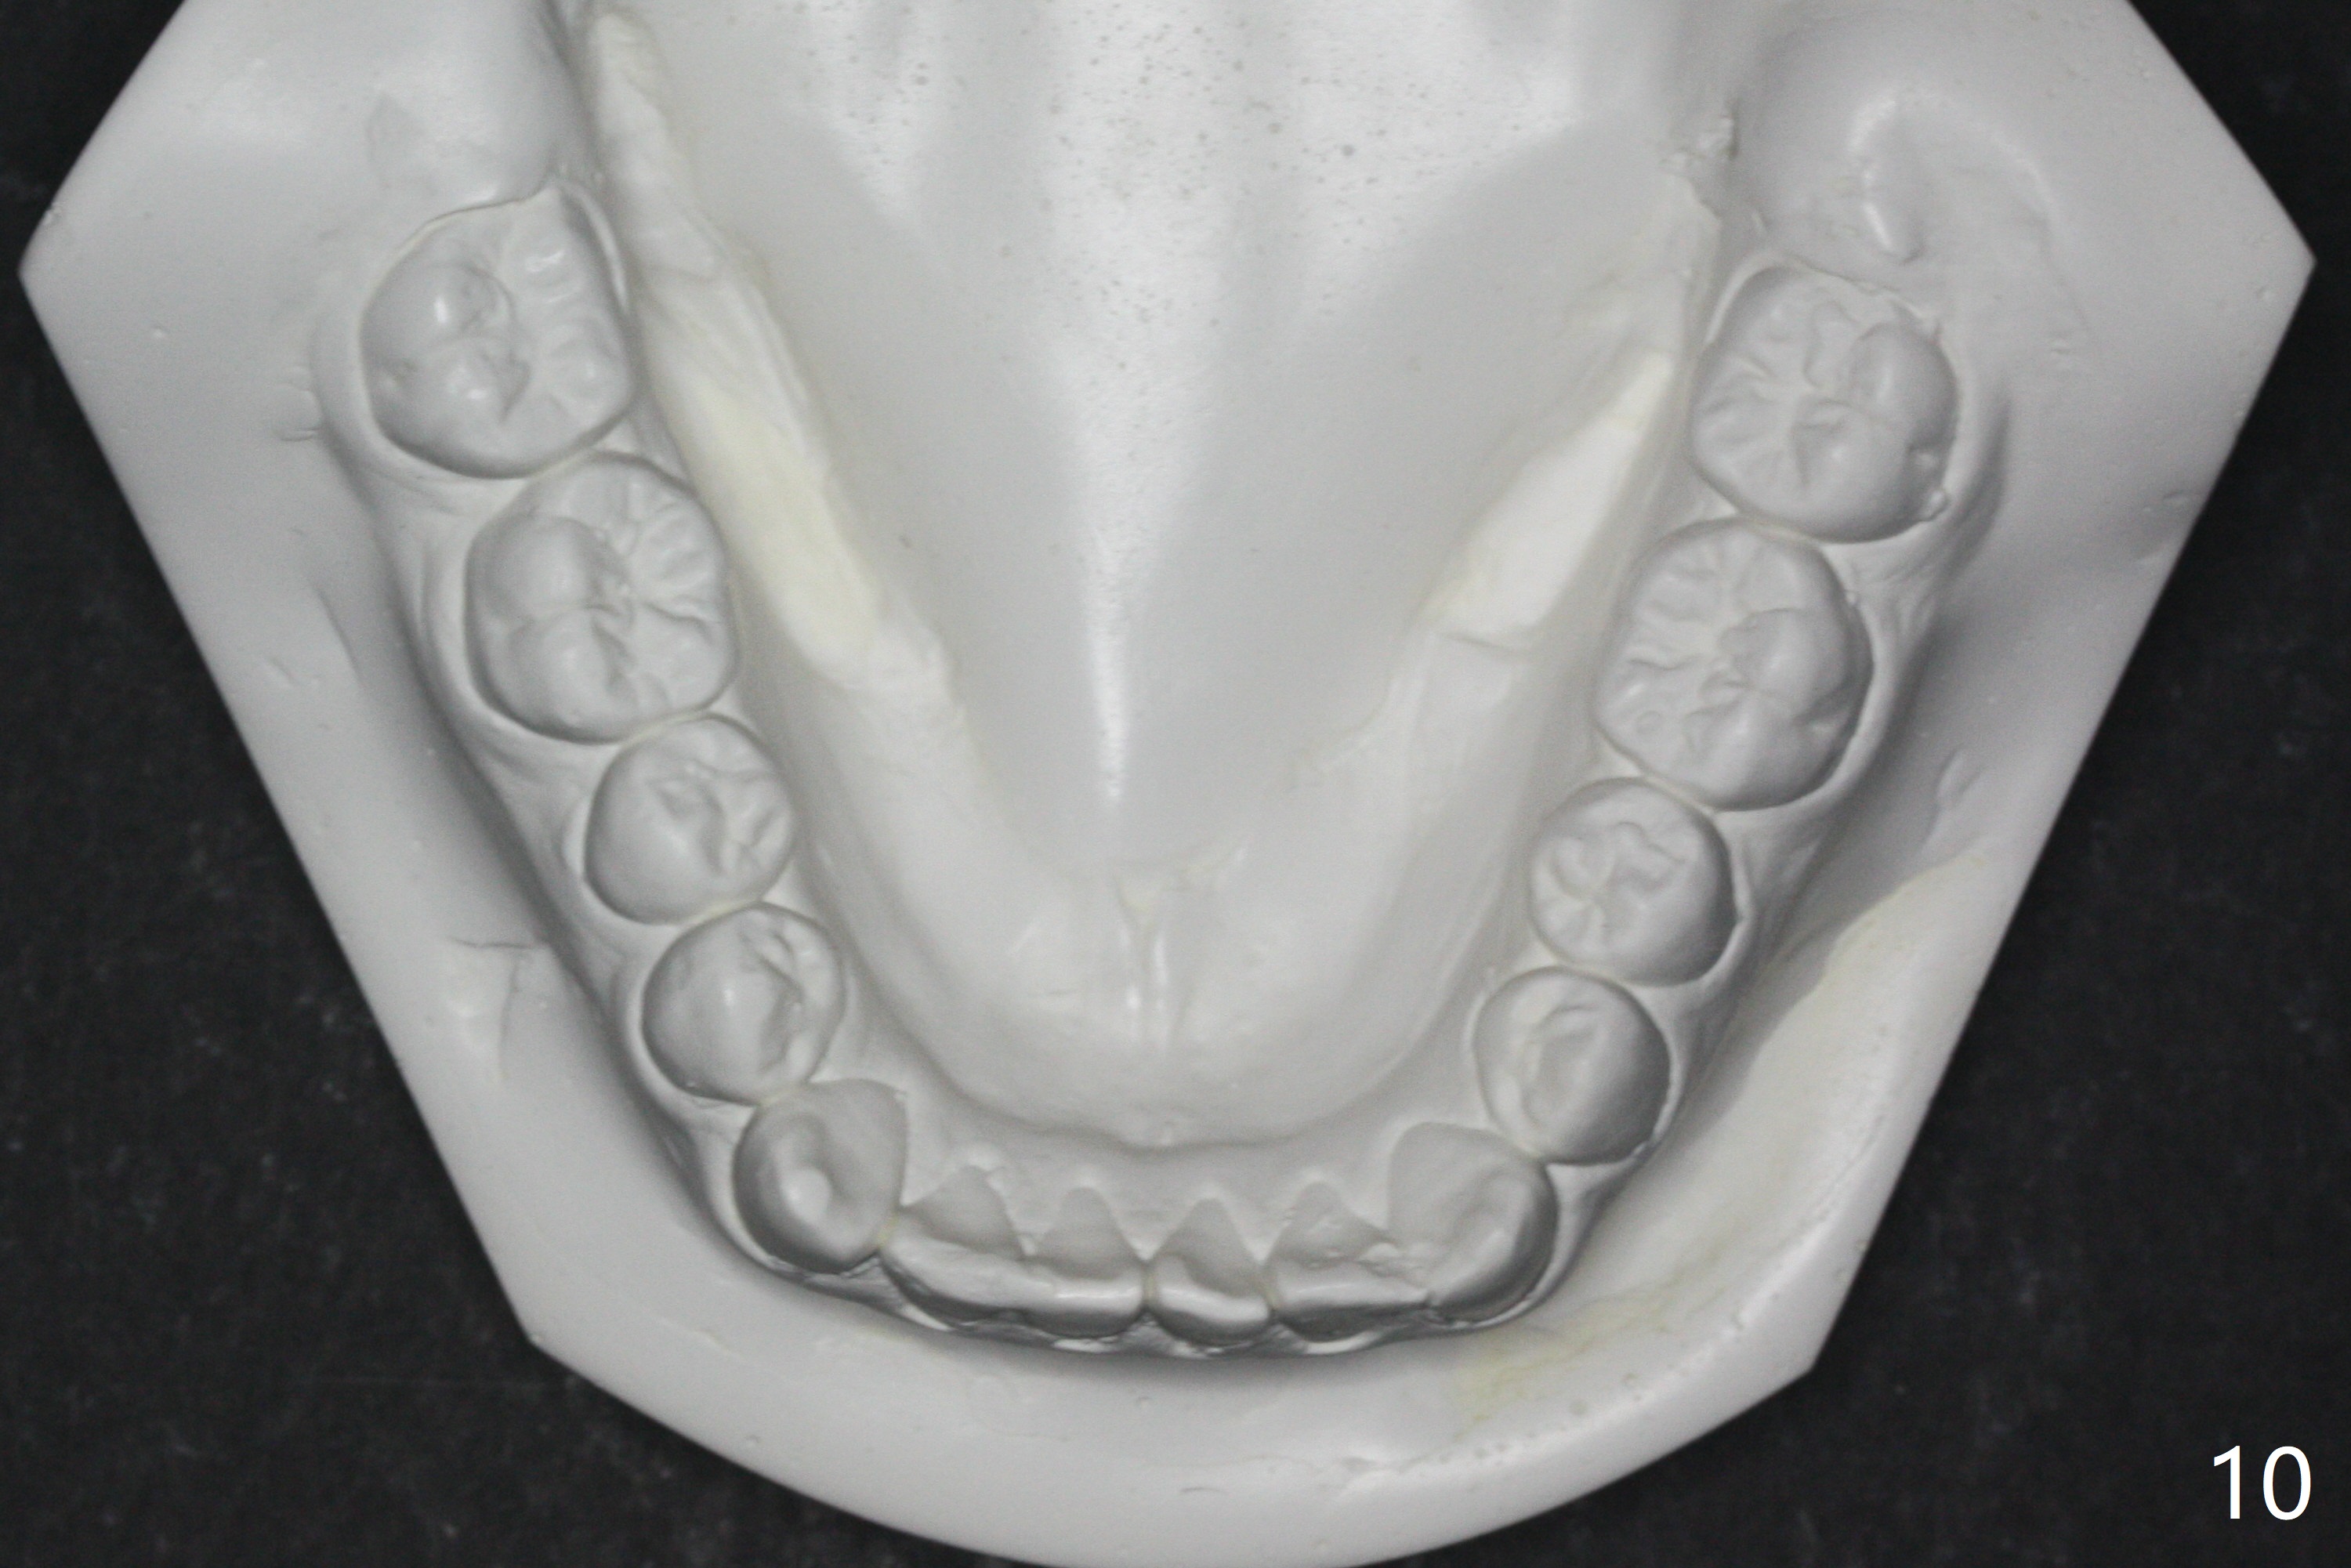

The upper dental midline of a 14-year-old man deviates the left (Fig.1,2,8) with midfacial concavity (Fig.3,4). The upper lateral incisors have cross bite, more severe on the left (Fig.6-8). Can we use open coil spring on the left first, a few months before the right, more or less to help correct the upper midline deviation? Cephalometric analysis shows Class III skeletal relationship (Fig.5,5',11).